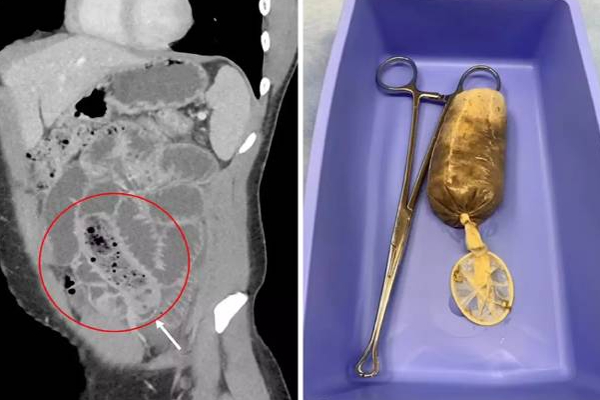

அவருக்கு சி.டி. ஸ்கேன் செய்த மருத்துவர்கள் அதிர்ச்சி அடைந்தனர். அதில், அவரது சிறு குடலில் ஆணுறையால் சுற்றப்பட்ட வாழை பழம் ஒன்று இருந்துள்ளது.

அந்த நபர், ஆணுறைக்குள் வாழைப்பழம் ஒன்றை வைத்து அதனை உட்கொண்டது தெரியவந்தது. பின்னர், அவருக்கு சிகிச்சை அளித்து, 3 நாட்கள் கழித்து இயல்பு நிலைக்கு திரும்பியுள்ளார்.

வயிற்றில் இருந்த அந்த வாழை பழத்துடன் கூடிய ஆணுறையும் நீக்கப்பட்டுள்ளது. இதன்பின்பே அவரால் வழக்கம்போல் சாப்பிட முடிந்துள்ளது.